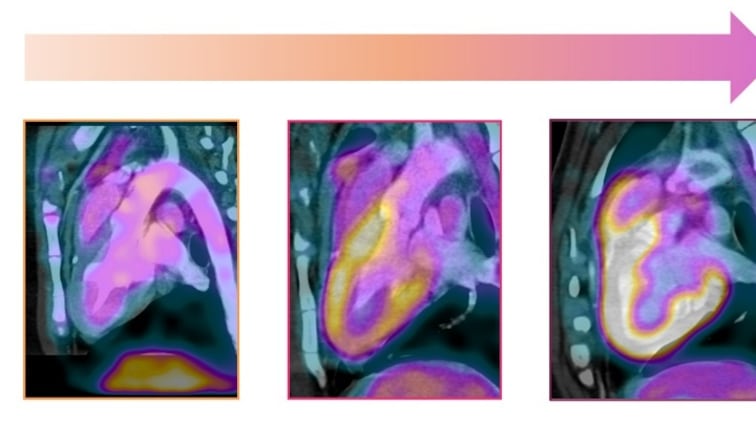

En este trabajo, realizado en un modelo experimental altamente similar al humano, el equipo indujo una sobrecarga de presión crónica en el corazón -equivalente a la hipertensión arterial- durante meses antes de administrar un régimen de antraciclinas comparable al utilizado en oncología clínica.

Los resultados fueron concluyentes, ya que los sujetos con sobrecarga de presión previa desarrollaron insuficiencia cardíaca con mucha mayor frecuencia que aquellos expuestos solo a antraciclinas.; además, presentaron mayor mortalidad y peor evolución general, reproduciendo fielmente las observaciones epidemiológicas humanas.